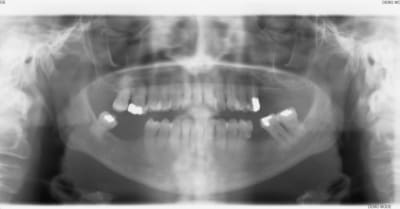

dans le même sujet, j'aurais aimé avoir votre avis sur ce cas. J'hésite entre une ROG avec membrane titane ou une greffe d'apposition.

04/11/2011 à 13h58

et pourquoi pas une expansion? tu as quoi, 14/15mm pour tes 2 implants? du fais 2 prémol? t'as pas besoin de diamètres super important amha...

j'ai 16mm entre les dents, mais 9mm de hauteur de crête pour la 47.

pour ce qui est de l'expansion, je n'ai jamais tenté l'exercice, et les corticales me paraissent bien épaisses.

Dans ce cas de figure, sans aucun doute, Régénération avec vis d'otéosynthèses ( en toile de tente) + membrane osseoguard résorbable.